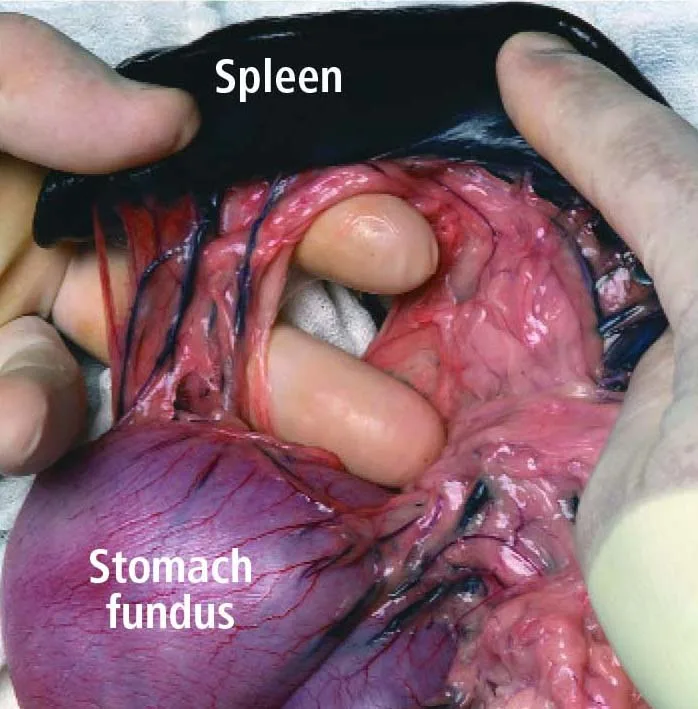

Step 5

Lift the stomach fundus out of the abdomen to expose the short gastric vessels tethered dorsally to the head of the spleen. From a cranial-to-caudal direction, loop an index finger around the tethering vessel group and bluntly punch a hole through an avascular area of the gastro-splenic ligament. The middle and index fingers are shown isolating the short gastric pedicle in a dog cadaver.